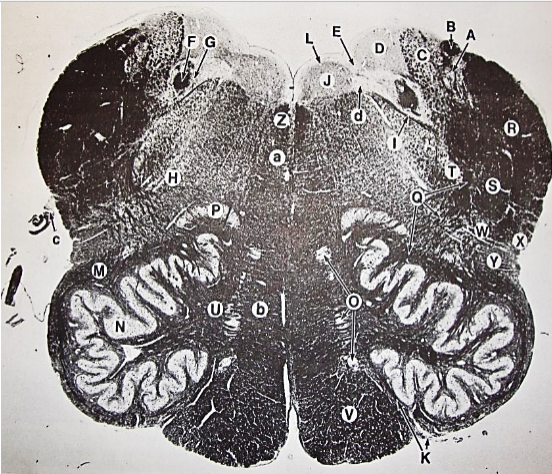

A

posterior median sulcus

B

posterior intermediate sulcus

C

anterior median fissure

D

gracile fasciculus

E

Gracile nucleus

F

fasciculus cuneatus

G

spinal trigeminal tract

H+I collectively

spinal trigeminal nucleus

J

Accessory nucleus

K

pyramidal decussation

L

lateral corticospinal tract

M

rubrospinal tract

N

posterior spinocerebellar tract

O

anterior spinocerebellar tract

P

lateral spinothalamic tract

Q

anterior spinothalamic tract

R

lateral vestibulospinal tract

S

medial longitudinal fasciculus

T

tectospinal tract

U

central canal